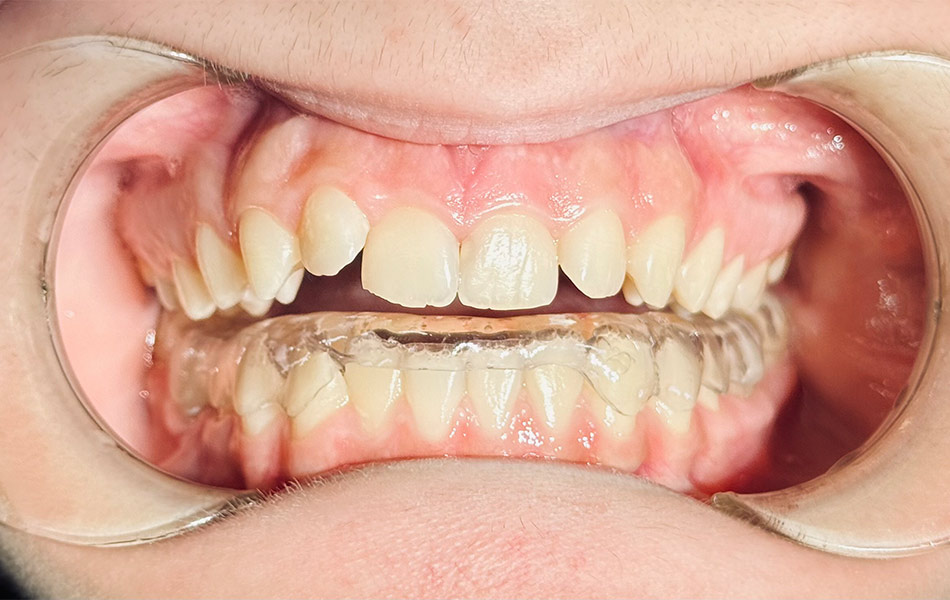

- Ограничение подвижности челюсти — специальные шины или сплинты для расслабления мышц;